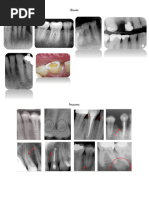

Técnicas Radiográficas en Odontología

Este documento describe diferentes técnicas radiográficas como la bisectriz y proyecciones oclusales. También explica conceptos de anatomía radiográfica como cemento, cámara pulpar y ligamento periodontal. Además, describe lesiones pulpares y periapicales, y trastornos del desarrollo dental como retención, fusión y geminación.

Mapas primer

Técnicas

radiográficas

Técnica de la bisectriz Proyecciones oclusales

Montaje de películas y

anatomía radiográfica

Anatomía Radiográfica Errores Radiográficos

Lesiones pulpares y

periapicales

Caries y Enfermedad

Periodontal